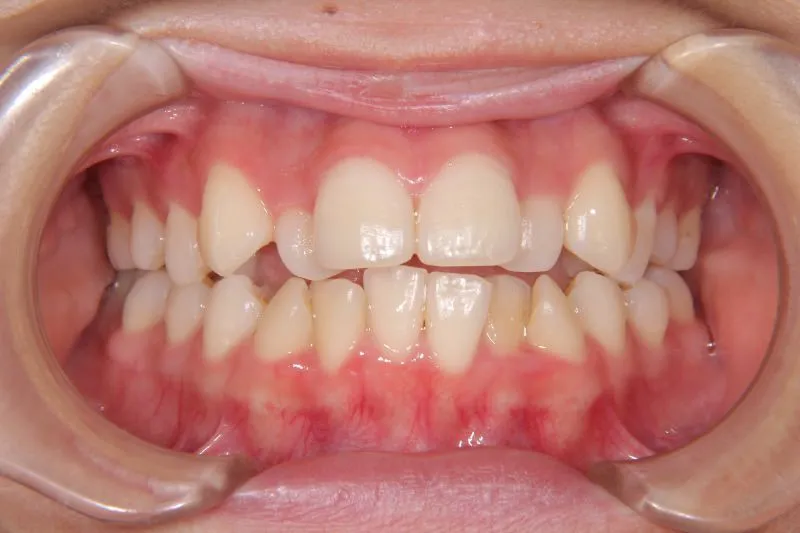

初診時年齢 高校生 (女性) 主訴 歯並びがガタガタ・口元の突出感

診断名 叢生・開咬・上下顎前突 装置名

特徴 ゆがんで生えている

状態 ガタガタ・でこぼこに生えている(叢生)

受け口(下顎前突/反対咬合)

前歯で噛めない(開咬/オープンバイト)

上下前歯、口元が出ている、口ゴボ(上下顎前突)

ガタガタの歯並びにお悩みの患者様でした。

口唇の突出感の他、下顎面高が長い印象も認められました。

歯科矯正アンカースクリューを用いた治療で、非抜歯で口唇突出の改善、臼歯の圧下、叢生の解消を図りました。

叢生は解消し、口元が大幅に引っ込み、下顎面高も縮小しました。

主訴が改善され、ご満足頂きました。